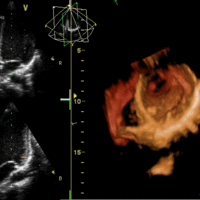

Cardiac Cycle

The cardiac cycle describes the heart's phases of contraction and relaxation that drive blood flow throughout the body.